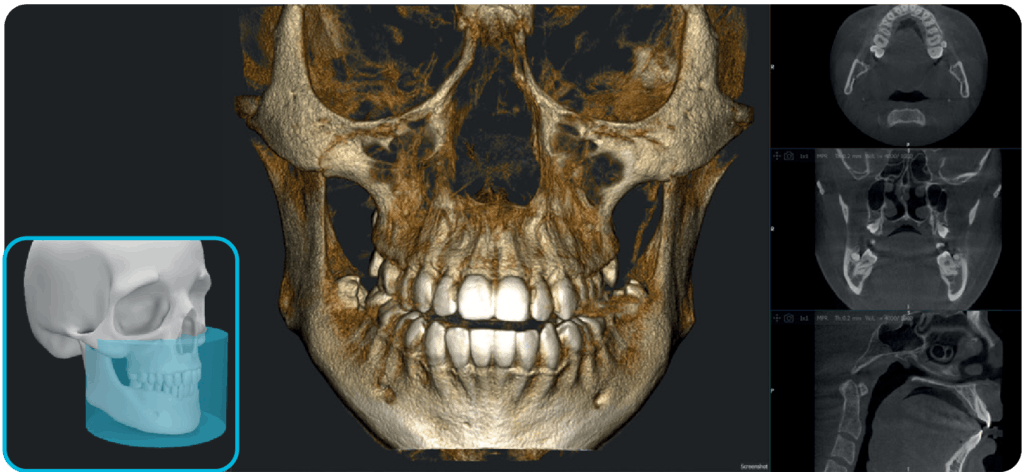

X-MIND® optima to połączenie nowoczesnych technologii w lekkiej, kompaktowej konstrukcji z innowacyjnym, łatwym w obsłudze oprogramowaniem RealGuide™ 5.4. Dzięki wykorzystaniu sztucznej inteligencji rozwiązanie to wspiera stomatologów na każdym etapie pracy – od precyzyjnej diagnozy, przez efektywne planowanie leczenia, aż po optymalizację wydajności pracy gabinetów stomatologicznych i usprawnienie komunikacji z pacjentami.

Dzięki szerokiemu zakresowi pól obrazowania (FOV) od 5×5 cm do 17×12 cm (Ø x H), urządzenie znajduje zastosowanie w różnorodnych zabiegach stomatologicznych – sprawdzi się zarówno w stomatologii ogólnej, jak i w specjalistycznych dziedzinach, takich jak implantologia, endodoncja, ortodoncja czy chirurgia szczękowo-twarzowa.

Idealne rozwiązanie dla skomplikowanych przypadków ortognatycznych, planowania implantów jarzmowych i chirurgii ortodontycznej.

X-MIND® optima łączy zaawansowaną technologię sprzętową z oprogramowaniem nowej generacji RealGUIDE 5.4, wprowadzając zalety sztucznej inteligencji do każdego etapu opieki nad pacjentem.

Oprogramowanie RealGuide 5.4 wykorzystuje technologię AI, aby maksymalnie ułatwić i usprawnić pracę lekarzom na każdym etapie leczenia implantoprotetycznego, zapewniając lepszą komunikację z pacjentami, budując zaufanie i poprawiając wskaźniki akceptacji leczenia.

Upraszczając złożone zadania i automatyzując kluczowe procesy, oprogramowanie usprawnia cały proces, umożliwiając szybsze i dokładniejsze planowanie leczenia.